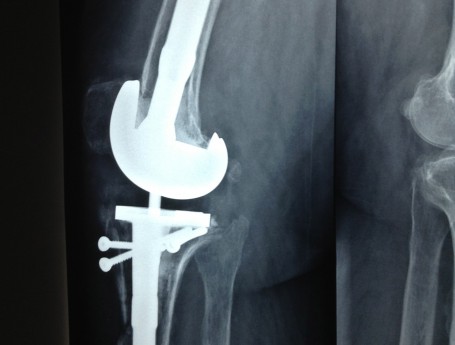

Revision Total Knee Replacement After Infection

• Revision Total Knee Replacement After Infection